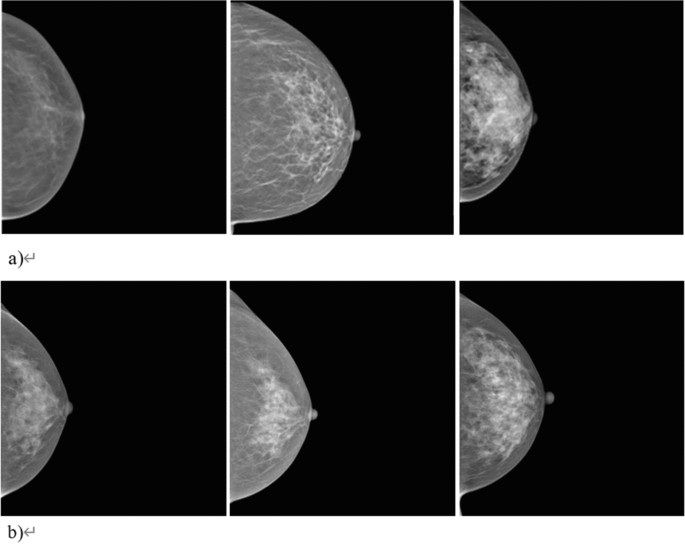

Figure 3 shows cases of true-positive (TP), false-negative (FN), false-positive (FP), and true-negative (TN) of breast cancer detection using anomaly detection method. For each of the four cases depicted, the images in each row represent the real image, one of the nine synthetic images that was most similar to the real image (projected image), and the difference map between the real image and the average of nine synthetic images.

Examples of anomaly detection with real mammographic image as an input (first image), one of the most similar nine normal synthetic mammographic images as an output (second image), and difference map between the real image and the synthetic image (last image). (a–d) Show true-positive, false-negative, false-positive, and true-negative case in order.